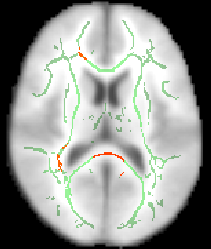

cd stats fslview all_FA -b 0,0.8 mean_FA_skeleton -b 0.2,0.8 -l Green

The -b option sets sensible display range options, and in the case of the skeleton image, also controls the thresholding applied. Now turn on the movie loop; you will see the mean FA skeleton on top of each different subject's aligned FA image. If all the processing so far has worked ok the skeleton should look like the examples shown here (see the TBSS paper for more examples of different subjects' results underneath the skeleton). If the registration has worked well you should see that in general each subject's major tracts are reasonably well aligned to the relevant parts of the skeleton. If you set the skeleton threshold (in FSLView, the lower of the display range settings) much lower than 0.2, it will extend away towards extremes where there is too much cross-subject variability and where the nonlinear registration has not been able to attain good alignments. Remember the skeleton threshold for the next stage.